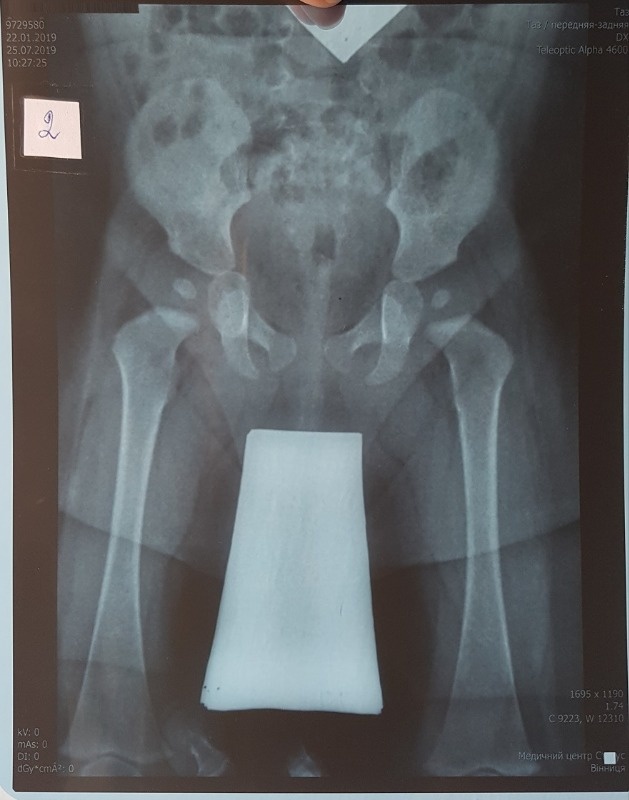

Основными жалобами, возникающими у владельцев, чьи животные подверглись дисплазии суставов, являются: снижение подвижности кошки, выраженная слабость конечностей, подвергшихся заболеванию, шаткая походка, хромота, неправильная постановка конечностей. В ходе проведения диагностических тестов ветеринарный врач на приёме выявляет выраженную болезненность и ограничение диапазона движений при ортопедическом осмотре. Однако, стандартом диагностики дисплазии суставов у животных является рентген-исследование с применением анестезии. Дело в том, что именно при достижении седации животного возможно придать правильное положение конечностям и суставам, чтобы дать объективную оценку наличию или отсутствию дисплазии исследуемой области костно-суставного аппарата кошки.

Рентгенограммы должны выполняться под седалгией или под наркозом, чтобы обеспечить нужное положение сустава. Стандартный рентгенографический снимок делается, когда собака находится в дорсальном положении с вытянутыми параллельно задними конечностями, колени повернуты так, чтобы коленная чашечка находилась в центре блоковой борозды и симметрично расположенным тазом. Вентродорсальный вид должен включать два поясничных позвонка и оба колена. Тяжесть клинических симптомов не соотвествует тяжести рентгенографических изменений. Рентгенографическая съемка под нагрузкой поможет количественно оценить степень слабости сустава.

Стандартный вид: кошка лежит на спине, а ее задние лапы вытянуты прямо. Этот вид похож на оценочную рентгенограмму, необходимую для подтверждения OFA степени дисплазии бедра. (OFA классифицирует бедра по семи различным категориям: отличное, хорошее, удовлетворительное, пограничное, легкое, умеренное или тяжелое.) Для сертификации PennHIP выполняются дополнительные обзоры, которые учитывают измерения дряблости суставов, а также конформации тазобедренных суставов.

Для постановки диагноза таз должен быть выровнен, а ноги выпрямлены. Это можно сделать только тогда, когда собака или кошка находятся под действием седативных препаратов.Берем два вида таза:

- VD (вентродорсальный) — на этом виде ваша собака лежит на спине, когда мы делаем рентгенограмму таза

- Боковой — на этом виде ваша собака лежит на боку

Это рентгенограммы таза трехмесячного щенка с явными пластинами роста. Разрывы в кости — это хрящи, которые не видны на рентгенограмме.

В возрасте 6 месяцев вы все еще можете видеть пластинки роста, но еще слишком рано ставить диагноз дисплазии тазобедренного сустава